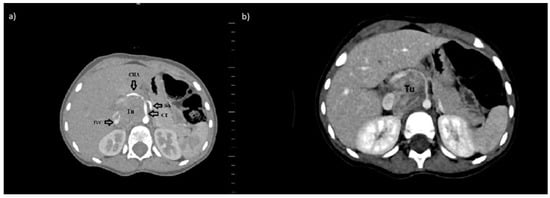

We present a retrospective analysis of the verification of radiological examinations performed on a 2.5-year-old boy with neuroblastoma. The boy was admitted to the hospital with a tumor in the abdominal cavity. Imaging examinations—ultrasonography (USG) and computed tomography (CT)—showed a solid mass, anteriorly from the right kidney and the thoracolumbar spine, ranging from Th11 to L3, with significant contrast enhancement. The lesion infiltrated the following organs: pancreas, the right adrenal gland, the liver’s visceral surface, the right kidney, the duodenum, the right side of the diaphragm, the right psoas muscle, and showing the neoplastic infiltration. The tumor compressed the inferior vena cava (VCI), which was about 2.5 cm away from the spine and was narrowed to 4 mm. Moreover, the tumor surrounded the following vessels: aorta (70–75% of the circumference), celiac trunk (100% of the circumference), common hepatic artery (100% of the circumference), superior mesenteric artery (100% of the circumference), VCI (50% of the circumference), right renal vein (50%), left renal vein (100%), splenic vein (50% of circumference), portal vein (50% of circumference). The dimensions of the lesion were: 4.9 cm × 4.6 cm × 7.3 cm (Figure 1a).

The control CT, which was performed eight weeks from the moment of diagnosis, showed the reduction of the tumor volume. The mass was 35% smaller (Figure 1b). The decision about resection with further postoperative chemo- and/or radiotherapy was made.

The INRGSS classifies neuroblastoma into the following: L1—disease is localized and does not involve vital structures, is limited to one body compartment and L2—a localized disease with positive IDRFs, M- distant metastases present, and MS- metastatic disease confined to the skin, liver, and/or bone marrow in children <18 months of age) [1]. According to the INRGSS classification, the presented patient was in group L2. Three IDRFs have been identified (the tumor encased aorta and vena cava, the origin of the celiac axis, and branches of the superior mesenteric artery at the mesenteric root) (Figure 1). That is why two cycles of chemotherapy were initially applied, resulting in a volume reduction of over 35%. Most patients in the L1 stage can be treated using surgery only. Barak et al. mentioned that 80% of the tumors, including high-risk neuroblastoma tumors, had total gross resection of the tumor with minimal operative morbidity and no mortality. Overall, 88% of children had greater than 90% resection of their lesion, and the three-year survival was 84% [3]. These results confirmed the sense of surgical treatment in our patient. Unfortunately, the postoperative complication related to the ligation of the vessel, which was identified as the vessel supplying blood to the tumor, resulted in many serious complications. In the postoperative angiography, this vessel was identified as a coeliac trunk. The coeliac artery and its branches supply blood to the spleen, pancreas, liver, stomach, and part of the duodenum. The precise knowledge of the localization of the celiac trunk in context to the tumor represents an essential prerequisite for the successful removal of the tumor [4,5]. Our patient presented type 1 of coeliac trunk variation (Figure 4).

Figure 1. Axial abdominal computed tomography scan in venous phase showed a retroperitoneal tumor in our patient a diagnosis (a) and after two courses of chemotherapy with Vepeside and Carboplatin (b). Abbreviations: CT—coeliac trunk, CHA—common hepatic artery, SA—splenic artery, IVC—inferior vena cava, Tu-tumor.